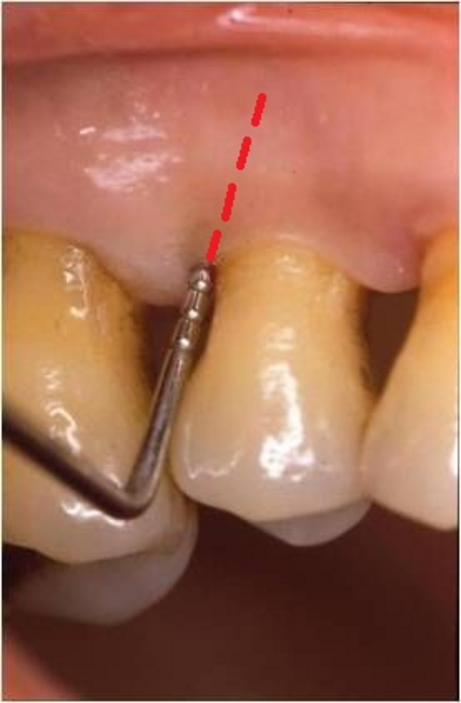

Radici dentali esposte sono il risultato della recessione gengivale. I denti in questi casi spesso sono sensibili a cibi e liquidi caldi, freddi o acidi. Le cause per cui si hanno recessioni gengivali sono le stessa da cui originano le parodontiti, prime tra tutte placca batterica, scarsa igiene orale, traumatismi, fumo. Esistono poi una varietà di fattori predisponenti che dovrebbero essere individuati per limitarne l’azione distruttiva e per prevenire l’ulteriore perdita di gengiva ed osso.

Innesti di tessuto molle possono essere utilizzati per coprire le radici esposte ma anche per ricostruire il tessuto che è andato perso. Il tessuto molle viene prelevato dal palato o da altre zone intraorali. L’intervento è quasi indolore e non esistono possibilità di rigetti. Il tessuto prelevato dalla zona donatrice si riforma spontaneamente in poche settimane.